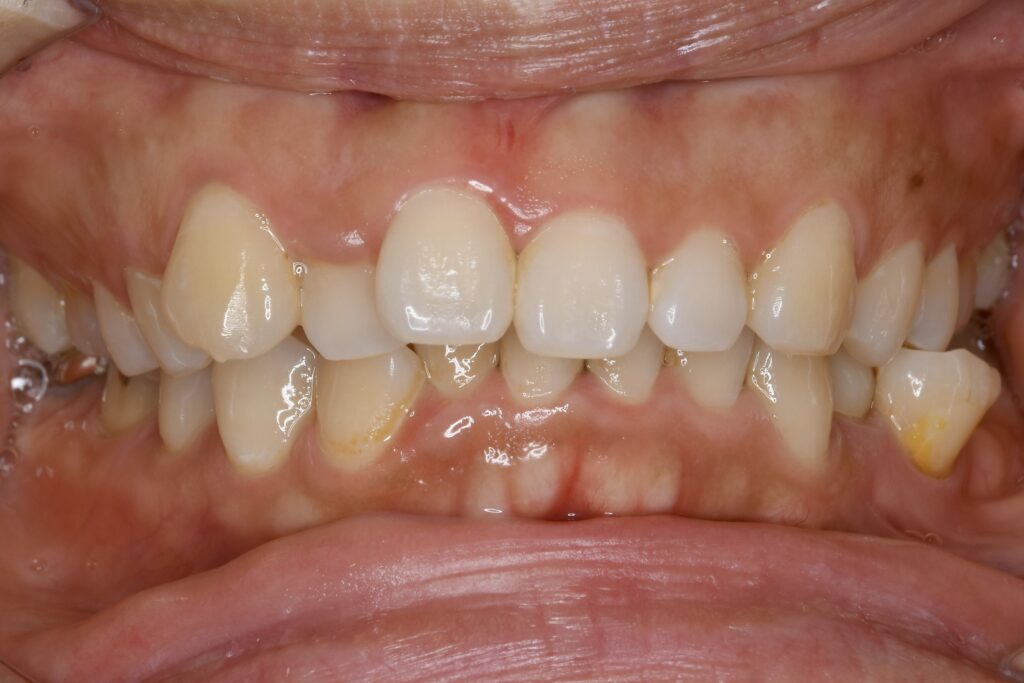

AFTER

• マウスピース装着時

主訴 口元が出ていて気になる。

治療内容 上下とも歯を2本抜いて、上の前歯を後方に引きながら、でこぼこを治しました。

使用装置 マウスピース矯正装置(インビザライン)

治療期間 1年7ヶ月